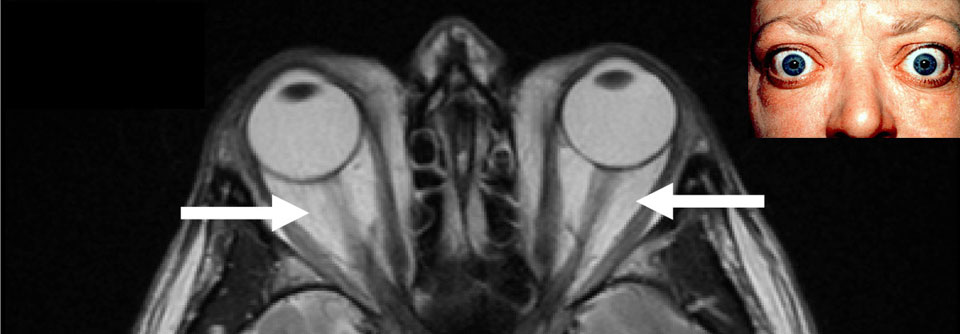

Die fortgeschrittene endokrine Orbitopathie ist gekennzeichnet durch einen Exophthalmus sowie eine Verminderung von Beweglichkeit und Sehvermögen. Therapeutisch kommt ein Eingriff infrage, in Zukunft womöglich auch ein monoklonaler Antikörper. Die fortgeschrittene endokrine Orbitopathie ist gekennzeichnet durch einen Exophthalmus sowie eine Verminderung von Beweglichkeit und Sehvermögen. Therapeutisch kommt ein Eingriff infrage, in Zukunft womöglich auch ein monoklonaler Antikörper. © Science Photo Library/Clinical Photography

Die endokrine Orbitopathie macht sich oft mit Schmerzen hinter dem Augapfel bzw. beim Auf-, Ab- und Seitblick bemerkbar. Objektiv fallen Entzündungszeichen wie Rötung der Augenlider und Konjunktiven sowie Chemosis und Karunkelschwellung auf. Für eine Progredienz spricht die Zunahme des Exophthalmus ebenso wie Verminderung von Beweglichkeit und Sehvermögen. Abhängig vom Ausmaß der Entzündung unterscheidet man drei Schweregrade: leicht, moderat und visusbedrohend (s. Kasten).